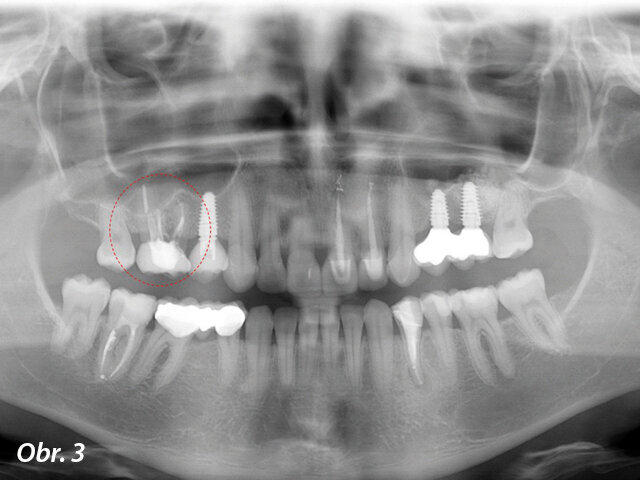

V listopadu roku 2017 se dostavila 39letá pacientka na vstupní vyšetření do White Clinic z důvodu bolesti zubu 16. Bylo provedeno klinické a radiografické vyšetření, včetně periapikálního snímku, CBCT skenu (Carestream 9600, Carestream Dental) a intra a extraorálních fotografií (obr. 1–3).

Při klinickém a radiografickém zhodnocení bylo zjištěno, že u zubu 16 byla přítomna cervikální resorpce v meziobukálním kořeni. Zvolený léčebný plán byl extrakce zubu a okamžité zavedení implantátu. Zub byl již v minulosti endodonticky přeléčen a ošetřen definitivní keramickou korunkou. Přestože je protokolem White Clinic zachovávání zubů, zub byl indikován k okamžité extrakci vzhledem ke stavu v dané situaci. Také z důvodu nedostatku času, nebyl náš digitální tým schopen vyrobit chirurgickou šablonu pro zavedení implantátu, proto zahrnoval léčebný plán chirurgickou fázi a digitální protetickou fázi.